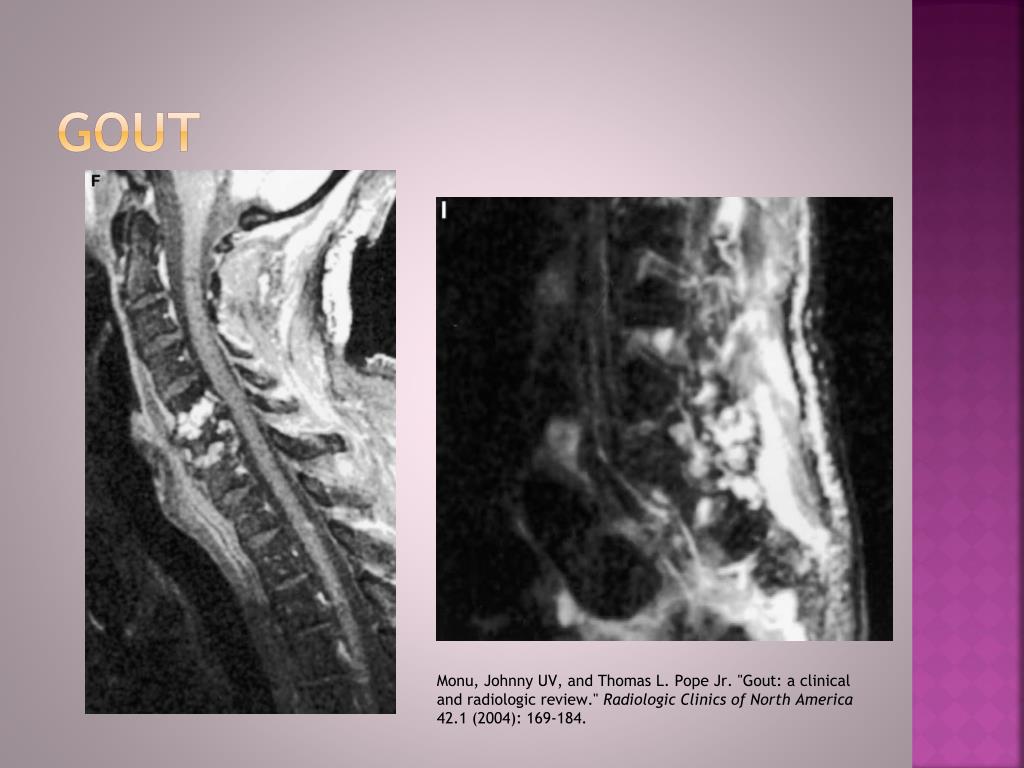

30. GOUT Monu, Johnny UV, and Thomas L. Pope Jr. "Gout: a clinical and radiologic review." Radiologic Clinics of North America 42.1 (2004): 169-184.

31. Gout